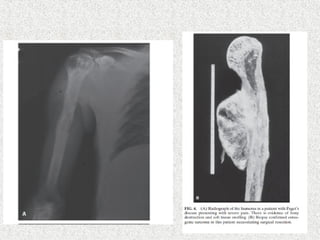

 X rays

 Transverse lucencies/pseudofractures

On the convex surface of weight bearing bone

 Focal bone resorption

 Disorded trabecular pattern

 Expanded bone

 Cortex thick

 Flame shaped/blade of grass osteolytic wedge

 sclerosis

 Pathological #